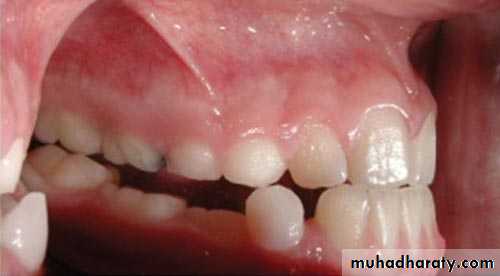

Extraction of Impacted Canine with Partial Bone ImpactionRadiograph showing an impacted maxillary canine with a labial localization

Clinical photograph of the area of impaction. The ischemic protuberance, shown by arrows, indicates the position of the crown of the impacted tooth